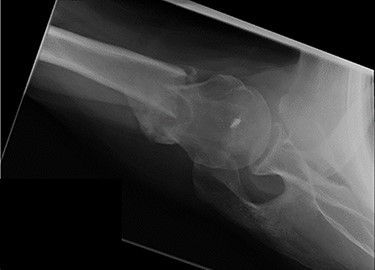

Review at 6 weeks post-injury demonstrated both clinical and radiological healing (Fig. 7). At a final 14-week review, the patient informed that he had returned to playing golf with no adverse symptoms. Examination revealed complete soft tissue healing over the fracture site and the range of movement was recorded as 120° of both abduction and forward flexion. Plain radiographs confirmed excellent fracture union, and the patient was discharged (Fig. 8).

Lateral scapula (Y) view X-ray taken 6 weeks post-injury showing radiological healing of the fracture.